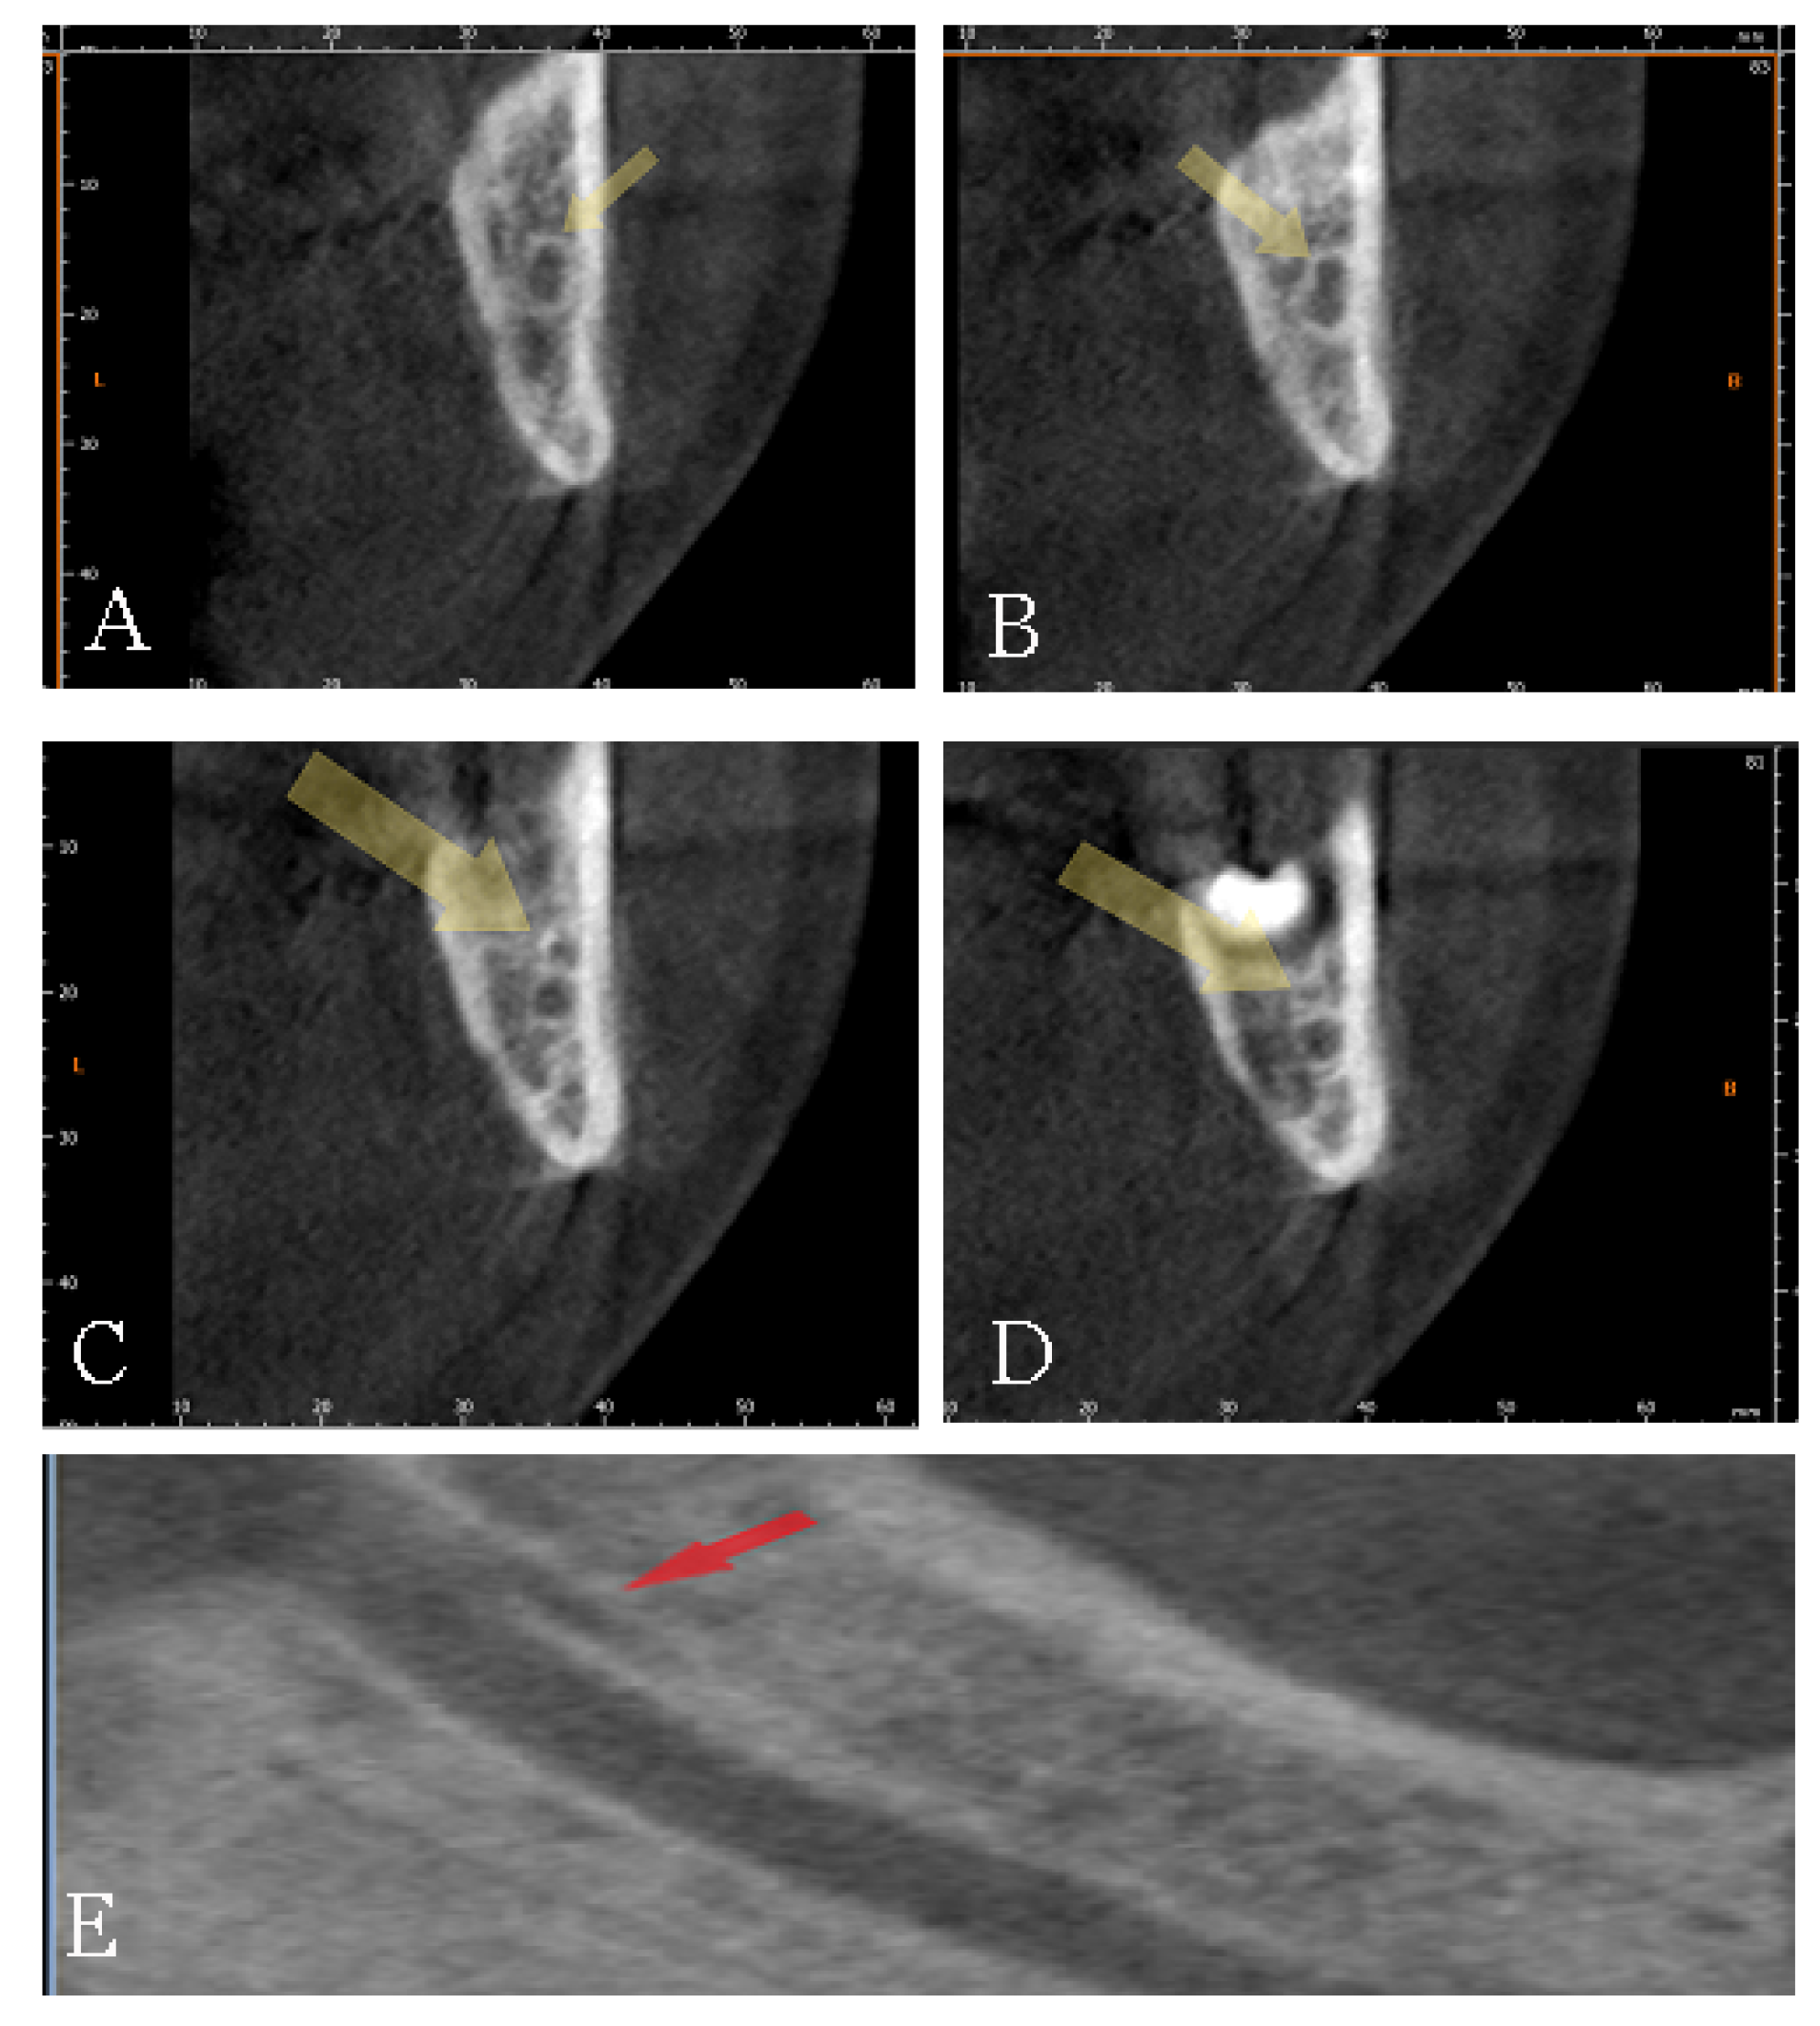

4.2. Bifid Canals: A Difficult Classification, Established Presence, and Clinical Implications of the Morphometric Data